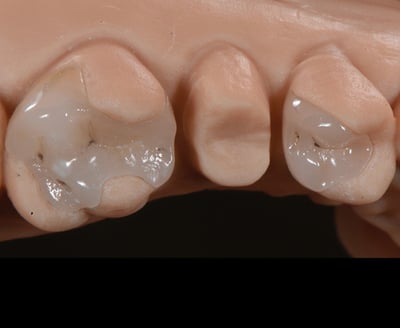

Zowel directe als indirecte, posterior restauraties kunnenuitdagend zijn, vanwege de hoeveelheid beschikbare materialen waaruit de behandelaar moet kiezen. De jonge patiënt in deze klinische casus had een losgekomen kroon op de tweede, bovenste pre-molaar en twee kapotte restauratiesop de eerste molaar en pre[1]molaar. Bij een meervoudige restauratie zoals deze moet een indirecte benadering worden overwogen. In dit geval is gekozen voor partiële, adhesieve restauraties van lithiumdisilicaat en een volzirkonium kroon. Verschillende materialen met verschillende indicaties, maar met gebruik van slechts één cement.

Beginsituatie en isolatie met rubberdam. |

Verwijderen van de oude amalgaamrestauratie (1e molaar) en composietrestauratie (1epremolaar) en schoonmaken van de caviteiten. |